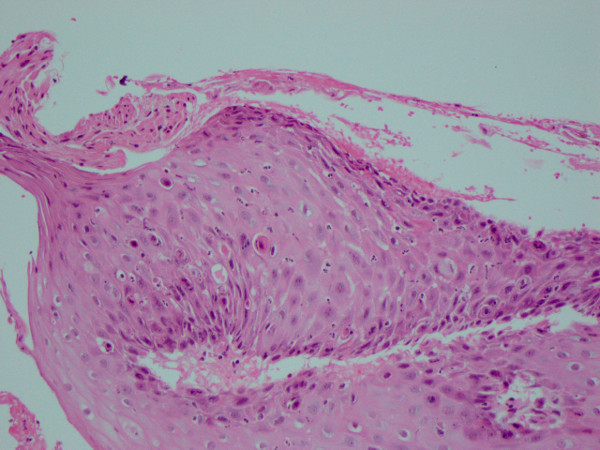

Due to the patient’s symptoms, an esophagogastroduodenoscopy (EGD) was performed which demonstrated mild mucosal erythema at the gastroesophageal junction (GEJ) and within the stomach. Histologically, numerous apoptotic bodies, mitoses, and ring mitoses were identified in the GEJ and gastric mucosa, highly suggestive of mitotic arrest and medication-induced injury or effect (Figures 1, 2, and 3). The glandular mucosa also had chronic active inflammation and Helicobacter organisms were identified. There was active inflammation and dykeratotic cells within the squamous mucosa at the GEJ (Figure 3). A review of the patient’s medications revealed the initiation of ixabepilone for the treatment of her metastatic breast carcinoma six months ago, with completion of 8 cycles. No further ixabepilone was administered after the biopsy results.